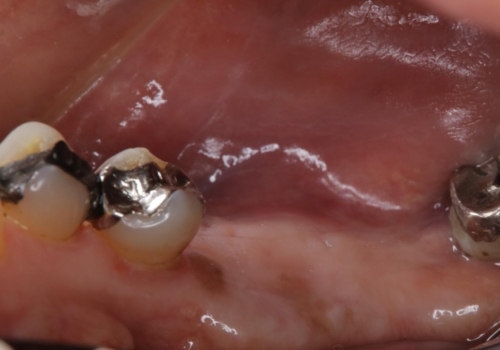

- 右下の奥歯が親知らずを除き2本とも無いため、インプラント希望で来院された患者様です。当院で2本インプラントを埋入し、右側でもしっかりと食事をしていただけるようになりました。